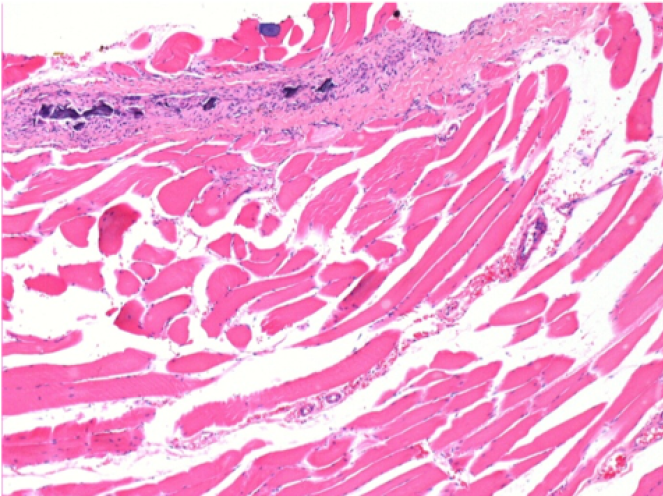

بعد 10 أيام من حقن إندوبيل

10 أيام بعد حقن إندوبيل 0.1 مل في العضلة أمام الظنبوب الأيمن.

هنا قد ترى تشكيل الفجوات التي تحيط بها الخلايا اللمفاوية. الفجوات تختلف عن نخر الأنسجة. يرتبط وجود الخلايا اللمفاوية بنفاذية أغشية الخلايا.

L : Control-100xD10

R:100xD10

R :200xD10

R :400xD10